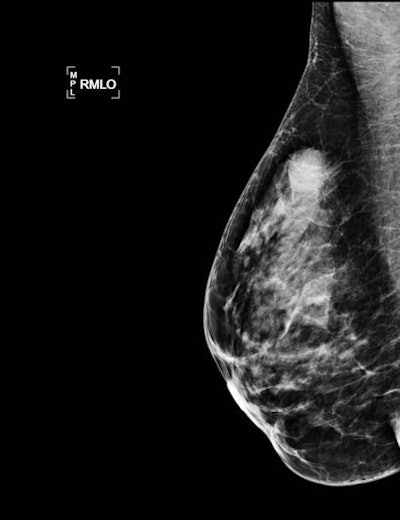

The most common imaging features were masses; nearly all were classified as BI-RADS 4 or 5. On mammography, microcalcifications alone accounted for 31% of the lesions. There were 42.6% luminal B, 24.5% luminal A, 19.1% human epidermal growth factor receptor 2 (HER2)-enriched, and 10.6% triple-negative (TN) tumors by immunohistochemistry. HER2 overexpression was correlated with the presence of calcifications at mammography (p = 0.03), the researchers found.

The most common abnormality on mammography was masses with or without microcalcifications (53.5%). Also, the researchers could precisely describe all the imaging characteristics and found masses were usually irregular and spiculated.

"For isolated microcalcifications, mammography is the only satisfactory investigation, and we insist on a high level of suspicion in young women with breast lumps shown to have microcalcifications, with or without a mass or density, in the region of the clinical finding," they wrote. "Finally, only two mammograms were classified as BI-RADS ACR 3. Contrary to previous studies pointing out that conventional imaging in young women is less likely to be called suspicious or malignant, we found a majority of BI-RADS 4 and 5 images."

Significantly more spiculated lesions were found in the luminal group, and the overexpression of the oncogene HER2 had a significant correlation with the presence of calcifications.

"[W]e think that in our study the predominance of luminal types is responsible for the high rate of irregular masses and the proportion of HER2+ cancers for the presence of microcalcifications," the researchers wrote.